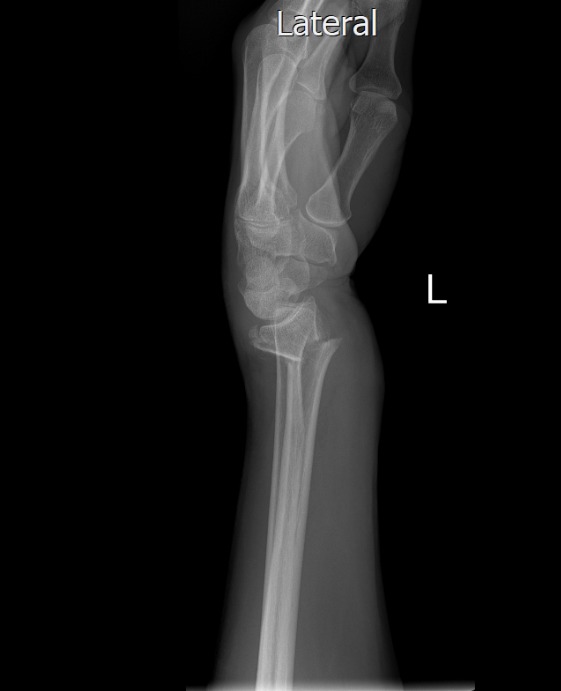

את קריאתו מגבה היועץ הרפואי בתמונות של שברים אמיתיות מהיממה האחרונה. "לא כדי להפחיד, אלא כדי להזכיר: החיים שווים הרבה יותר מהרגע המסוכן הזה".

בהתייחסו לתמונות השברים אותן הציג הוא אומר "כל תמונה של שבר היא סיפור של חיים שנעצרו בבת אחת – ניתוחים, גבס, שיקום ממושך, כאבים בלתי פוסקים ואובדן שגרה. תראו לעשות הכל, בעיקר המבוגרים, בכדי שלא להגיע לרגעים הללו חלילה".